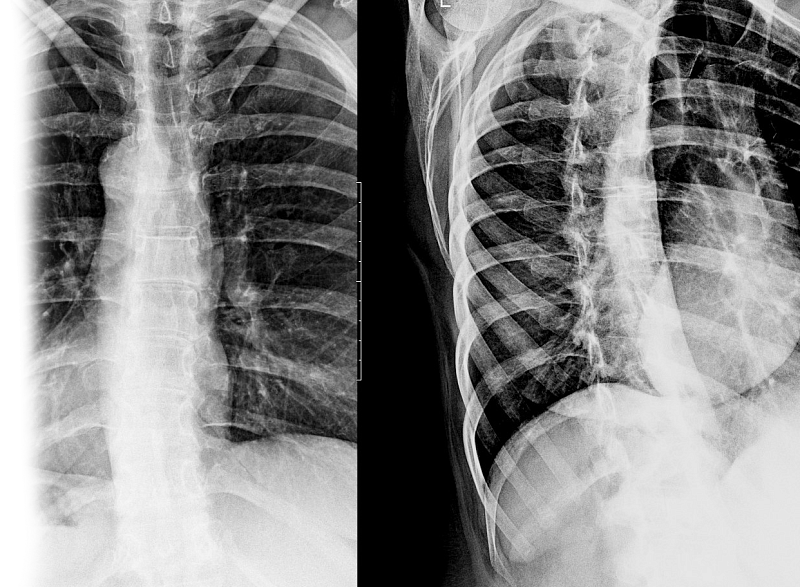

Рентгенография одного отдела позвоночника в косых проекциях – дополнительный вид исследования, который позволяет оценить состояние отдела позвоночника.

Диагностическая услуга выполняется в одной или двух проекциях.

Исследование позволяет получить дополнительную информацию по анатомической локализации патологических изменений.